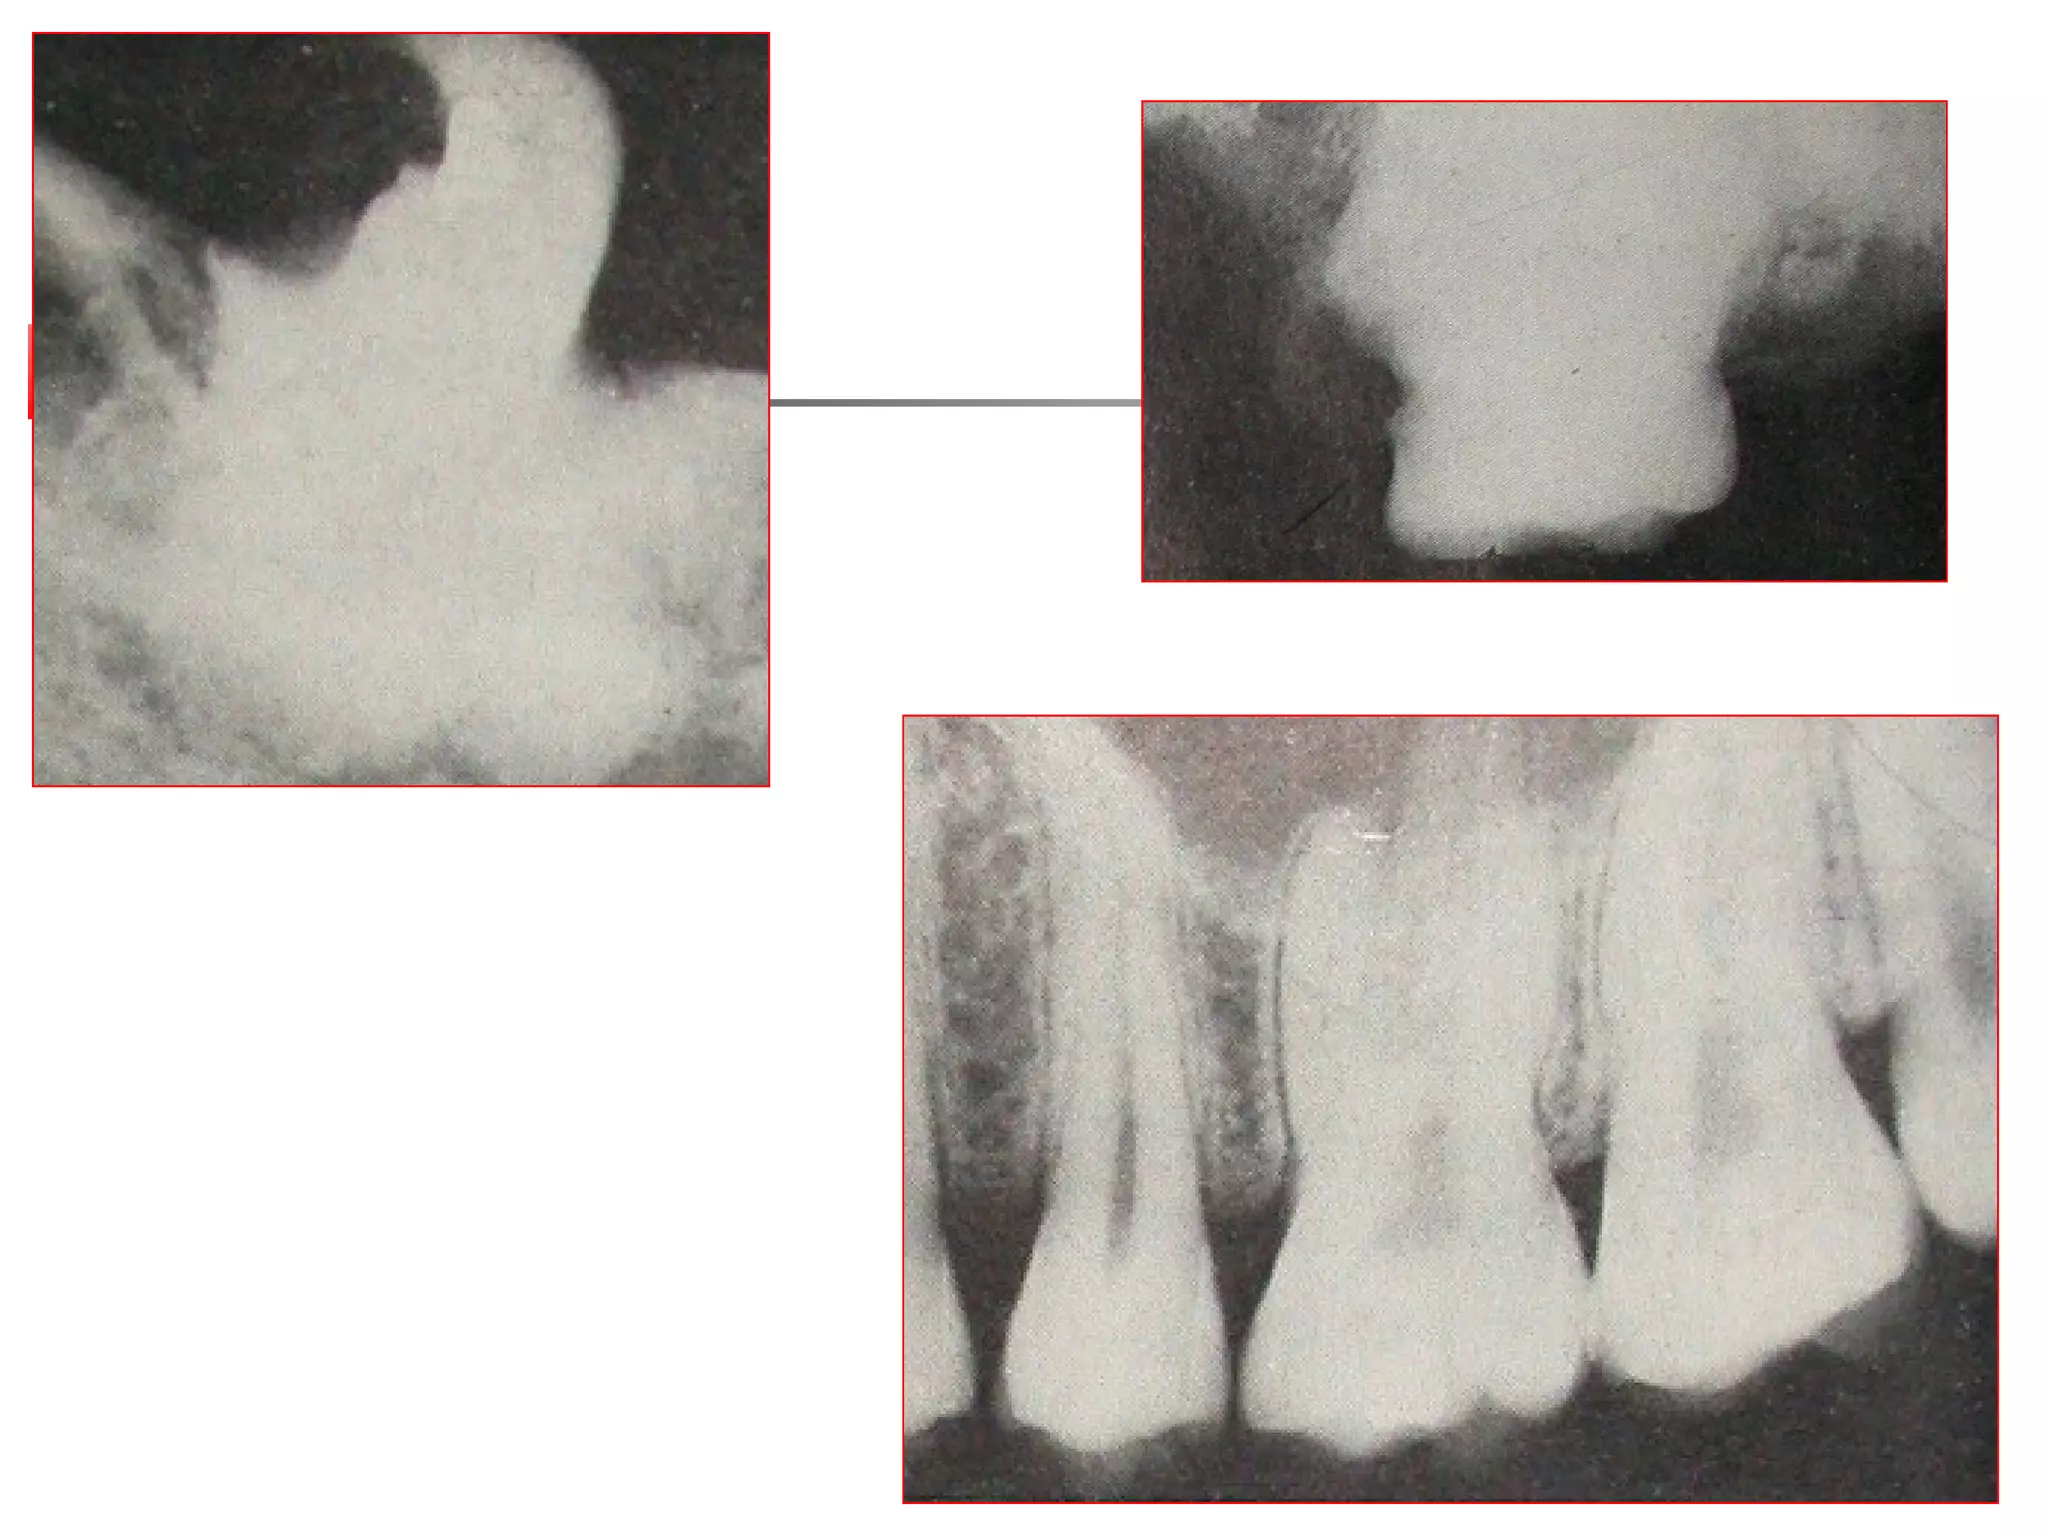

 Root has to be located either clinically or

radiographically